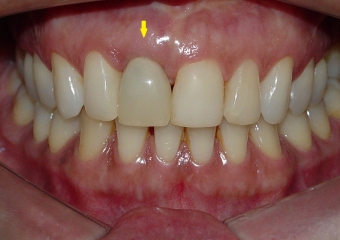

Imagem inicial de paciente com fratura de raiz no dente 11

Sorriso inicial